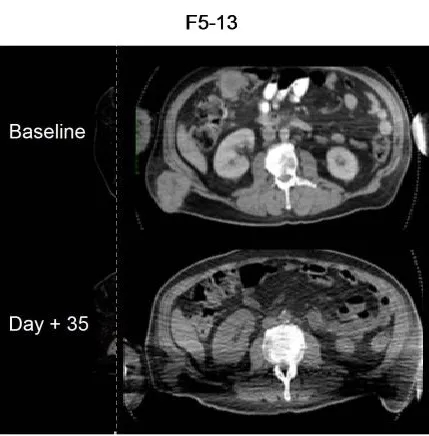

另一例患者(F5-13)经TCR-T+DC癌症疫苗联合治疗第35天的PET/CT显示出初始抗肿瘤活性,CT扫描可见大型皮下/肌肉转移灶消退(详见下图4)。

▲图源“Clin Cancer Res”,版权归原作者所有,如无意中侵犯了知识产权,请联系我们删除